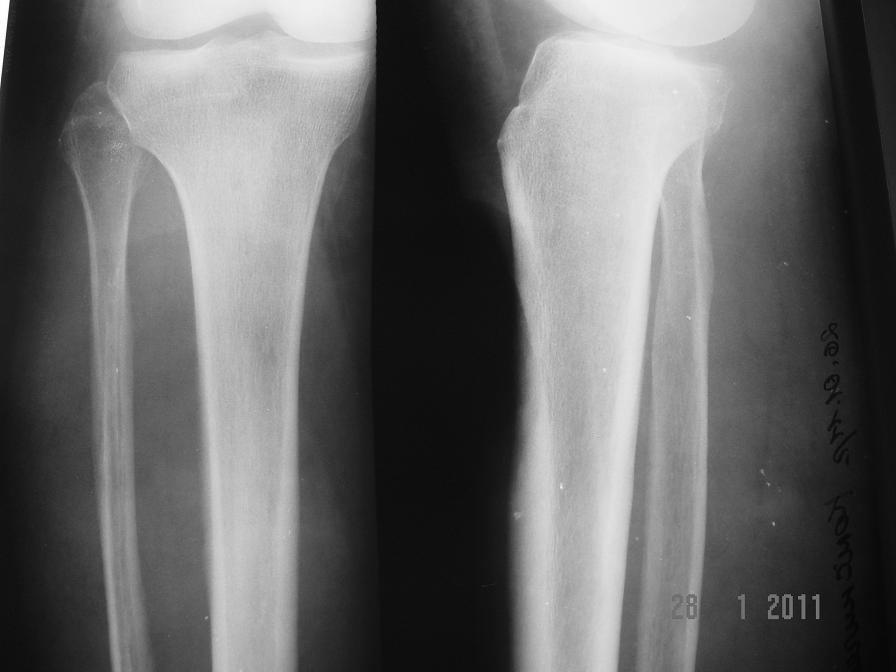

РТГ - 1

По предложенной им классификации, это повреждение называется «поздняя лучевая язва» и из всех локальных лучевых повреждений относится к наиболее тяжелым.

Ее особенности: 100% инфицированность бактериями, 100% наличие радиационного остеонекроза подлежащей кости, частое перерождение краев язвы во вторичную злокачественную опухоль.

Исходя из этого и должна складываться тактика лечения: края и дно раны должны быть радикально иссечены и отправлены на гистологическое исследование, подлежащий участок кости резецирован, выполнена пластика дефекта.

По механизму возникновения поздняя лучевая язва - это спонтанный некроз тканей в центре постлучевого фиброза+полная неспособность тканей, подвергшихся постлучевому фиброзу к регенерации. Поэтому язва и прогрессирует до размеров всего облученного участка.